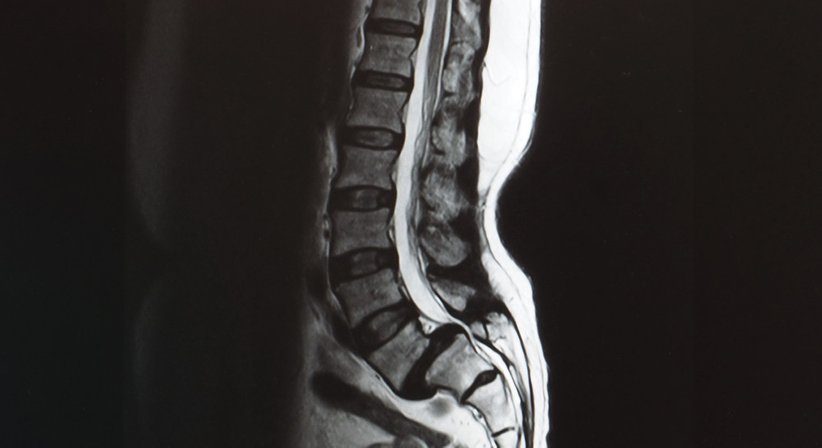

Die Sagittalebene ist jene gedachte Ebene, die den Körper von vorne nach hinten (sagittal) "durchschneidet". Die sagittale Balance auf Basis eines ausgewogenen sagittalen Profils ermöglicht uns das aufrechte Stehen ohne wesentlichen Energieaufwand; umgekehrt können sagittale Dysbalancen und Störungen des sagittalen Profils zu steigenden Anforderungen an die Muskulatur, Überlastungen, Behinderungen und einer Abhängigkeit von Gehhilfen und letztlich zu einer merklichen Beeinträchtigung der Lebensqualität führen.

Ein ausgeglichenes sagittales Profil ist von großer Bedeutung für eine normale Funktion der Wirbelsäule, weswegen es besonders wichtig ist, dem Erhalt und der Korrektur des sagittalen Profils bei der Diagnostik und Behandlung von Deformitäten und bei stabilisierenden Operationen an der Wirbelsäule besondere Beachtung zu schenken und Behandlungen vorausschauend und so zu planen, dass Störungen der sagittalen Balance bestmöglich vermieden werden.

Als Facharzt für Orthopädie und Orthopädische Chirurgie setze ich mich seit vielen Jahren intensiv mit dem Thema der sagittalen Balance auseinander. Zur Beurteilung und Diagnostik von Deformitäten der Wirbelsäule wird die Wirbelsäule exakt vermessen und die sagittalen und spinopelvinen Parameter (Parameter der Wirbelsäule, des Beckens; die Beziehung zwischen Wirbelsäule und Becken ist von großer Bedeutung für die sagittale Balance) werden genau bestimmt, sodass bereits im Vorfeld möglichst genau abgeleitet werden kann, wie und wo Korrekturen erfolgen müssen, um die sagittale Balance und damit auch die Bewegungsfreude und Lebensqualität bestmöglich wiederherzustellen.